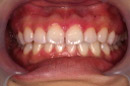

| 最後に比較の写真を撮影します | |||||||||